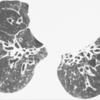

Bronchiectasis

Gough section

Date: 06/06/2004

Views: 4951